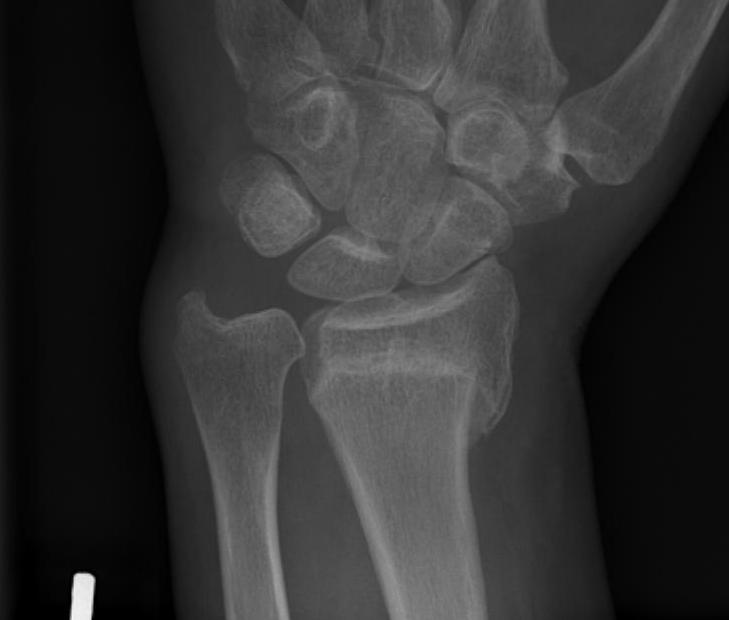

Xray

Bilateral xrays

PA film in neutral

- wrist neutral

- elbow & shoulder at 90°

malunion